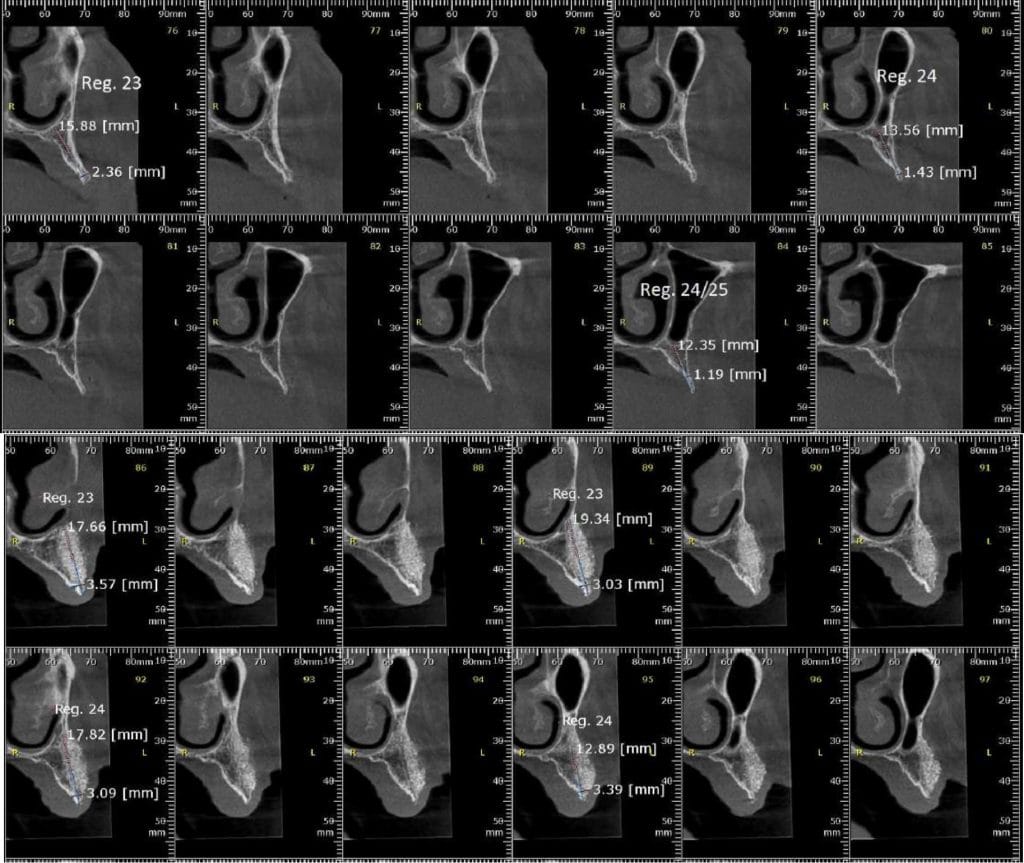

Olá colegas, aqui está um caso didático de reconstrução óssea total da maxila, levantamento do seio maxilar bilateral e bloqueio espesso com aplicação do conceito de PRF e Biotensigrity.

Após 6 meses de maturação óssea e implantes instalados com torque médio de 35 N / cm2.